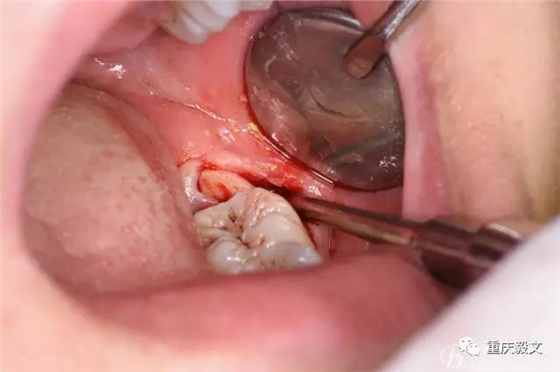

圖5.分離舌側(cè)牙齦

圖6.分離頰側(cè)牙齦,目的使牙冠和牙根能順利從牙齦軟組織脫位。

圖7.高速渦輪鉆分牙

圖8.先從頸部橫斷38